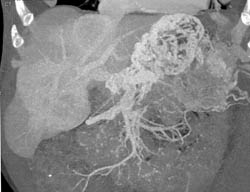

Pancreatic Cancer Occludes the PV/SMV